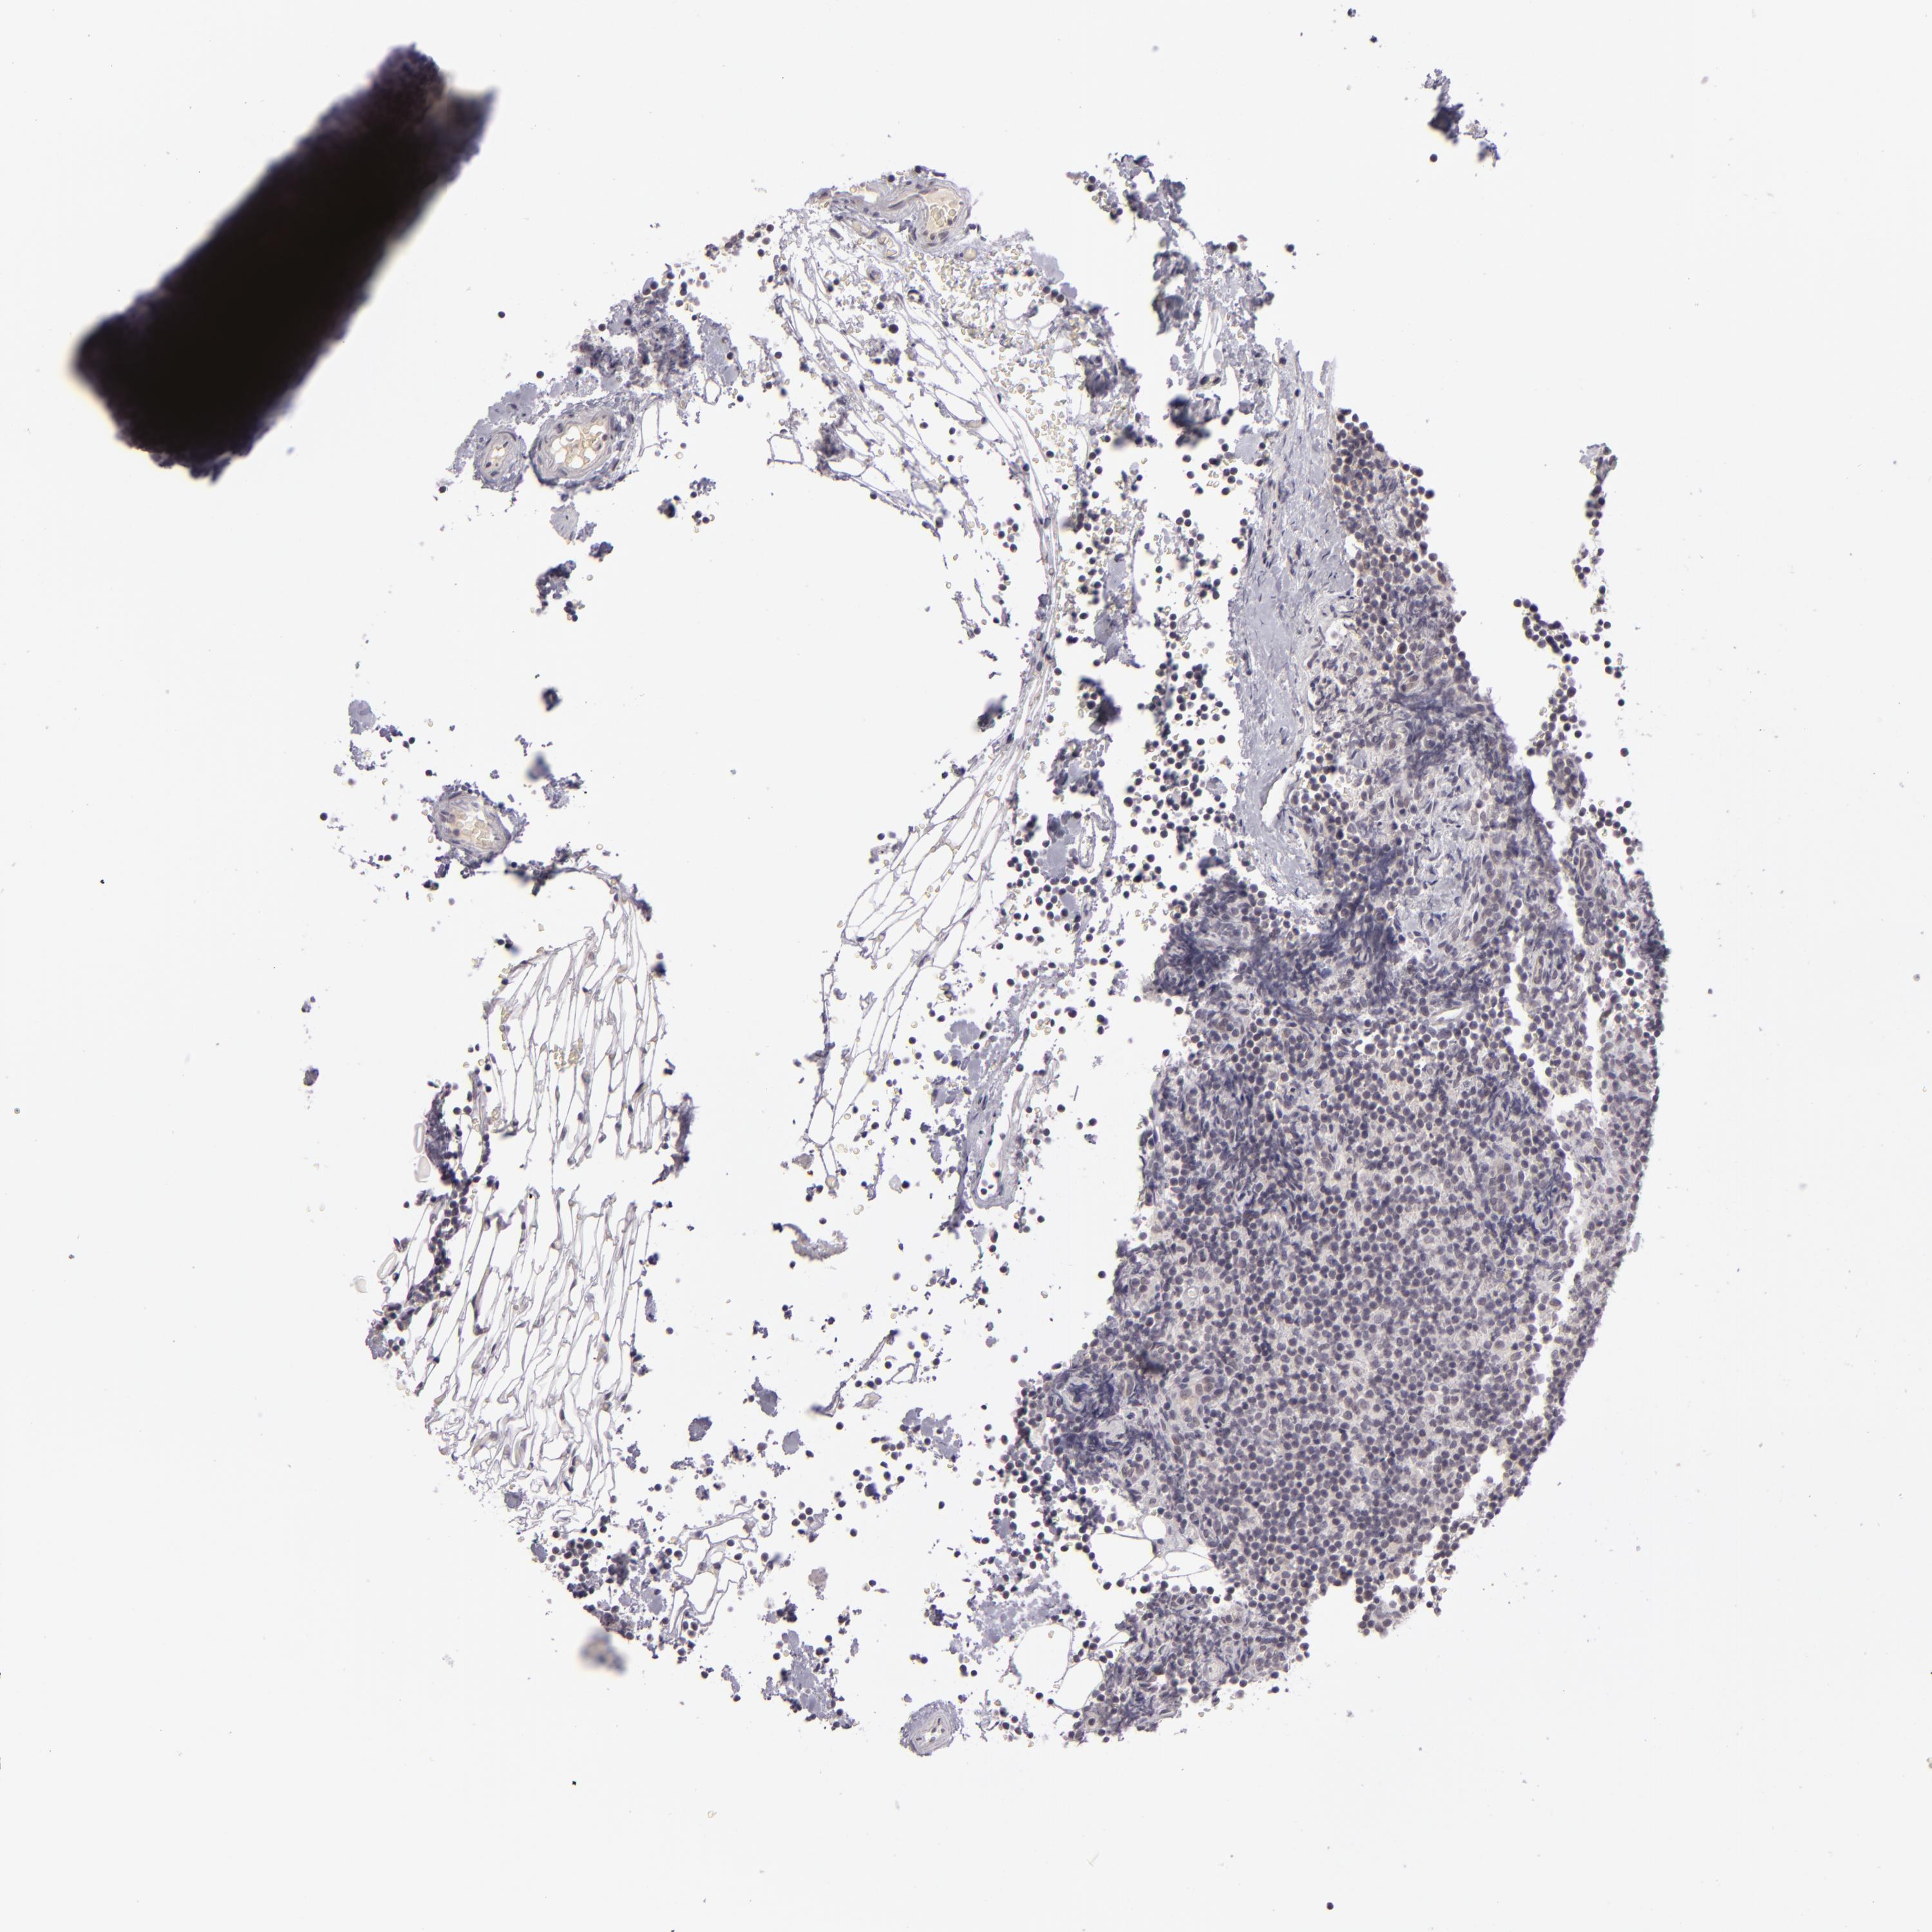

LYMPHOMA - Protein expressioni

A mouse-over function shows sample information and annotation data. Click on an image to view it in a full screen mode. Samples can be filtered based on level of antibody staining by selecting one or several of the following categories: high, medium, low and not detected. The assay and annotation is described here.

Each image is clickable and will lead to virtual microscopy that enables deeper exploration of all samples and also displays staining intensity scores, fraction scores and subcellular localization as well as patient and tissue information for each sample.

Antibody HPA001791

Staining

High

Intensity

Strong

Quantity

>75%

Location

Nuclear

Malignant lymphoma, non-Hodgkin's type, High grade

Hodgkin's disease, NOS

Malignant lymphoma, non-Hodgkin's type, Low grade